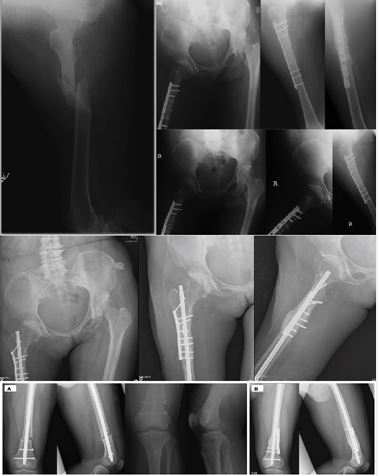

Case 1 – Shear-prone proximal femoral nonunion after intramedullary nailing

A patient with a proximal femoral fracture initially underwent IM nailing. Alignment and length were restored, but the construct left a long oblique fracture line at the metaphyseal–diaphyseal junction with a relatively wide canal–nail mismatch. Clinically, the patient reported persistent pain and difficulty weight-bearing; radiographs demonstrated hypertrophic callus with an unbridged lateral cortex and subtle toggling of the proximal fragment, consistent with a shear?dominated gap environment.

Revision surgery consisted of adding a short non-locking 3.5-mm dynamic compression plate through a limited lateral approach, spanning the fracture with two bicortical screws per segment. No nail exchange was performed. The plate was positioned to neutralize shear and rotational drift rather than to create absolute compression. At follow? up, radiographs showed progressive bridging of the lateral cortex and maturation of callus, and the patient regained functional weight-bearing with pain relief (Figure 4). Post- operatively, the Radiographic Union Score for Hip (RUSH) improved to 10 at 6 months, and the Visual Analog Scale (VAS) for pain decreased from 8 pre-op to 1.

Case 2 – Post-polio femoral hypertrophic nonunion

A poliomyelitis?affected limb with long?standing muscular imbalance sustained a femoral shaft fracture. Initial fixation using a lateral plate with cerclage wiring failed; plate breakage occurred under cyclical loading with loss of alignment and progression to hypertrophic nonunion. Radiographs demonstrated exuberant callus but persistent lucency at the fracture site and mechanical instability.

Revision treatment consisted of inserting an IM nail to restore axial alignment and length, combined with a short non-locking lateral plate acting as an anti-shear buttress over the nonunion site. The plate was deliberately kept short, with a limited number of bicortical screws, to avoid converting the system into an overly rigid load?bearing construct. Following revision, the patient progressed to radiographic union with gradual consolidation of the fracture line and improved function (Figure 5). The RUST score progressed from 4 at revision to 11 at final follow-up.

Case 3 – Distal femoral metaphyseal fracture

Case 3 highlights a challenging mechanical zone: distal- third (infra?isthmal) diaphyseal/metaphyseal femoral fractures, where the medullary canal widens and the distal segment is short. Even with acceptable radiographic alignment, the nail–canal mismatch and proximity to the knee can permit disproportionate bending and rotational micromotion, predisposing to delayed union or nonunion [7–9]. A distal femoral fracture with an oblique, shear-prone geometry was initially treated with antegrade IM nailing. Despite adequate reduction, progressive hypertrophic callus with a persistent fracture line suggested ongoing shear at the metaphyseal interface.

Because antegrade nailing is most forgiving at the mid-shaft/isthmus, distal-third fractures have traditionally pushed surgeons toward retrograde nails or bulky distal femur plating. Here, we used the shear-shielding strategy to expand the usable envelope of antegrade nailing: a very short non-locking lateral plate was placed as a buttress to neutralize transverse shear and torsion at the distal segment while retaining axial load sharing through the nail. The construct progressed to consolidation without the morbidity of nail exchange or escalation to a long distal femur plate (Figure 6).

Case 4 – Correction of symptomatic rotational malalignment after femoral IM nailing

The fourth case illustrates that the same nail– plate ‘vector control’ principle can be applied beyond nonunion treatment, specifically for torsional instability and malalignment. A 14-year-old female sustained a femoral shaft fracture from a motorcycle accident and underwent antegrade interlocking nailing at an outside hospital. After fracture pain improved, she developed a symptomatic out?toeing gait. Computed tomography torsion measurements demonstrated substantial external rotational malalignment: the injured femur measured 28° external rotation compared with 5° on the contralateral side (23° malrotation). At 16-month follow-up, CT confirmed near-symmetry of torsion (injured 7° vs contralateral 5°), and the patient’s gait normalized.

At 16-month follow-up, CT confirmed near-symmetry  of torsion (injured 7° vs contralateral 5°), and the patient’s gait normalized.

This integrated theoretical and clinical series reframes hypertrophic nonunion and other ‘failed’ constructs as problems of directional mechanics rather than global stiffness alone1. To rigorously define this mechanism, we map the fracture mechanobiology as a dynamical system in a phase space portrait (Figure 7).In this visualization, hypertrophic nonunion is not merely a biological failure but a system trapped in a “Hypertrophic Attractor”—a high-shear zone where stochastic transverse noise (Δy) prevents the biological algorithm from converging to union. Standard exchange nailing often fails to escape this attractor because it addresses scalar stability without filtering directional noise. Conversely, the shear-shielding nail-plate construct acts as a vector-specific filter. As illustrated by the intervention trajectory in Figure 7, this strategy does not aim for absolute rigidity (the origin) but effectively steers the system state vertically out of the “Shear Trap” and into a “Pocket of Reducibility” (Osteogenic Window). Within this pocket, defined by minimized shear but preserved axial dynamization, the otherwise computationally irreducible healing process becomes algorithmically predictable. The shear?shielding nail–plate construct selectively increases resistance to transverse displacement and rotation while maintaining axial load sharing, thereby modulating the mechanobiological signals that drive callus maturation [1–4]. Case 3 is particularly instructive because infra?isthmal/distal?third femoral fractures are mechanically disadvantaged for antegrade nailing due to canal widening and a shorter distal segment; radiographic studies identify these features as predictors of nonunion and emphasize the importance of distal fixation density [7–9]. Our approach extends the functional range of antegrade nailing into the distal third by adding a minimal, low-profile buttress that targets Δy and torsion. Case 4 further shows that the same vector?control logic can be leveraged to correct and stabilize rotational malalignment while preserving the original nail, avoiding more extensive revision constructs [15–17]. These observations align with broader clinical and biomechanical literature demonstrating that augmentative plating with the nail retained improves rotational stability and can outperform exchange nailing in femoral shaft nonunion [10–12].